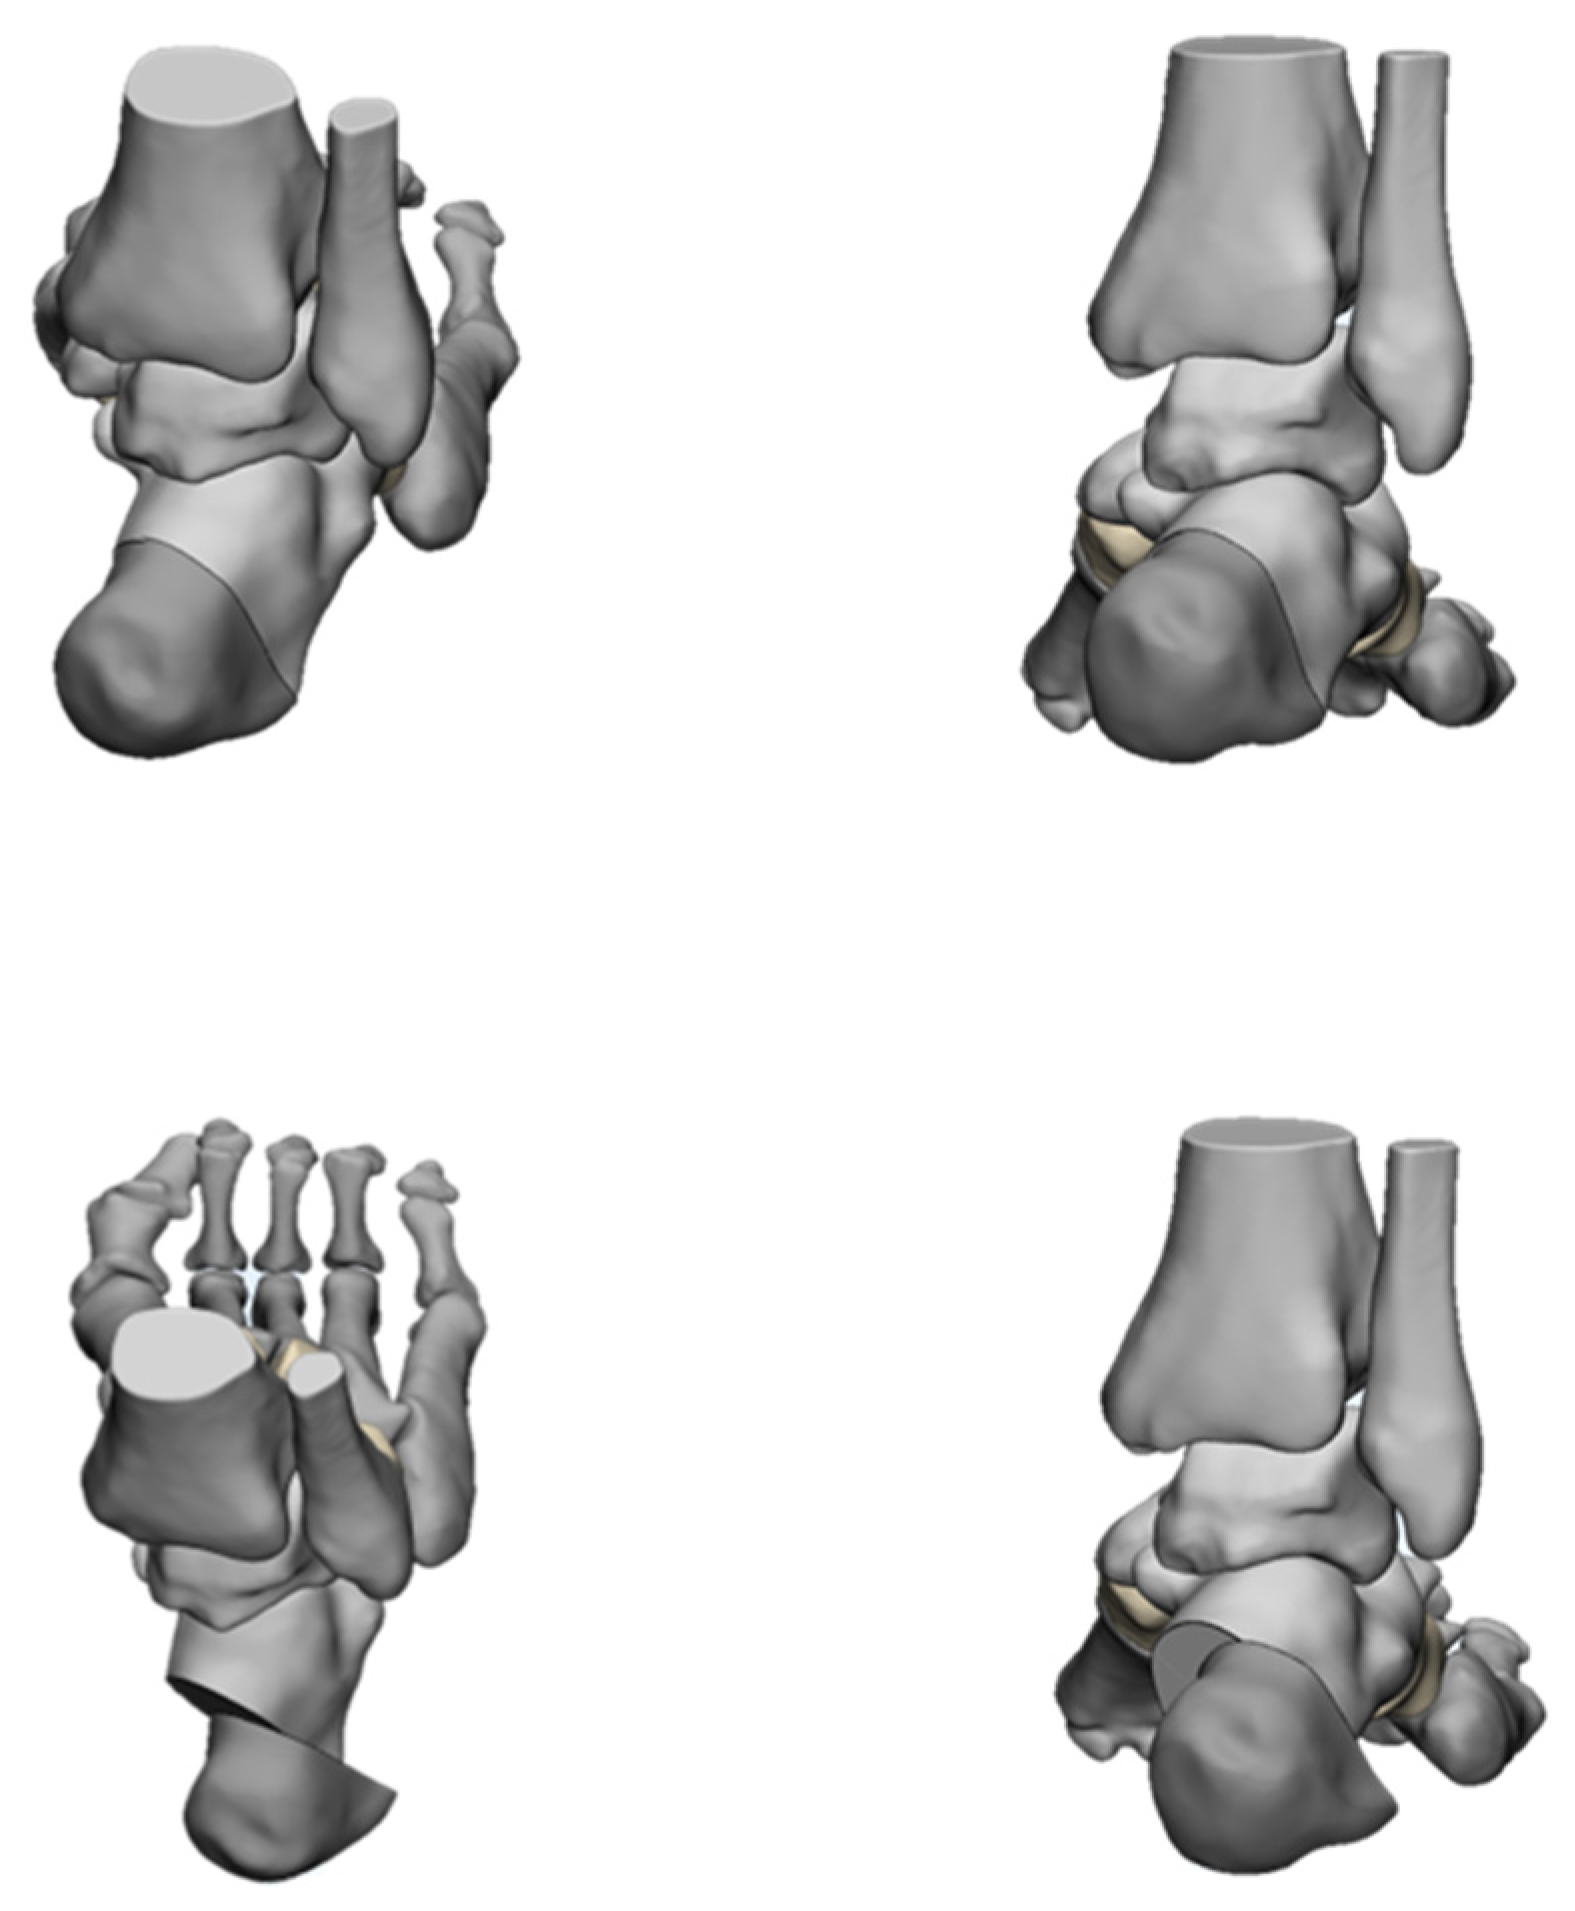

4.2. Radiological Evaluation

- An, T.; Haupt, E.; Michalski, M.; Salo, J.; Pfeffer, G. Cavovarus With a Twist: Midfoot Coronal and Axial Plane Rotational Deformity in Charcot-Marie-Tooth Disease. Foot Ankle Int. 2022, 43, 676–682. [Google Scholar] [CrossRef]